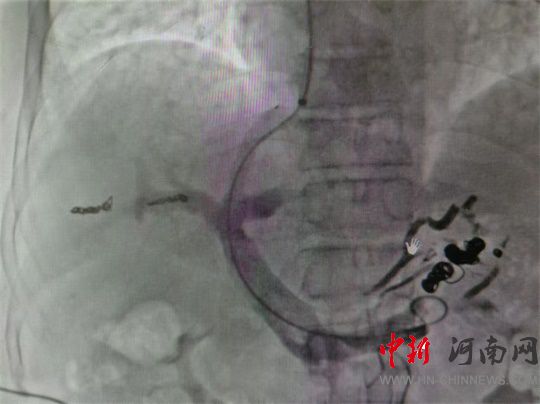

DSA下門靜脈造影

經(jīng)頸靜脈肝內(nèi)門體分流術(shù)

胃冠狀靜脈栓塞術(shù)

通過右側(cè)頸動脈穿刺

引入動脈鞘、導(dǎo)管

造影顯示

胃冠狀靜脈

血管極度紊亂

經(jīng)導(dǎo)管注入血管膠

及不同直徑

栓塞彈簧圈

封堵破裂血管

(導(dǎo)管開通分流道)

隨后串聯(lián)

門靜脈血管

與肝靜脈血管

架橋成功

手術(shù)順利